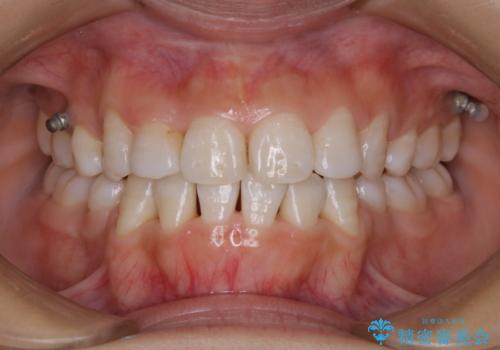

- クリーニングをしてほしいとのことで来院されました。

PMTC30分コースを行いました。

全体的に着色がついていました。

歯の面に凹凸があるため、着色が付きやすい患者様です。1-2カ月に1回のペースでクリーニンングを行っています。